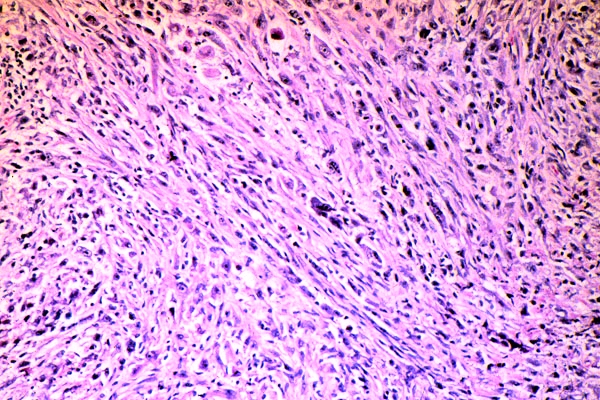

Malignant mesothelioma, microscopic appearance. Malignant mesotheliomas may be composed of mesothelial/epithelial like cells or malignant spindle cells resembling a sarcoma. Malignant mesotheliomas may also have a biphasic pattern (including spindle cells and mesothelial/epithelial cells).